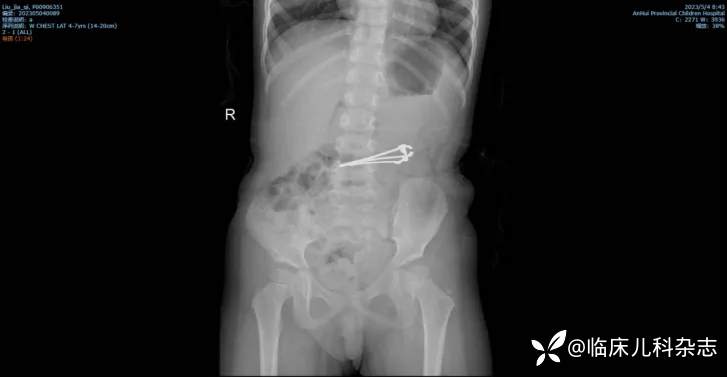

尖锐异物(如缝衣针、枣核、刀片)易引起消化道黏膜损伤、溃疡、穿孔、瘘、憩室等并发症,甚至包括纵隔感染及胸腹腔感染。